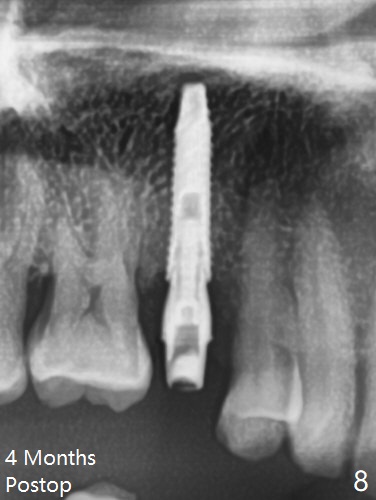

A 61-year-old man cracks the tooth #4 while chewing on a piece of chicken bone (Fig.1,2). Initial osteotomy appears to be able to hold a 16 mm long implant (Fig.3). After sequential osteotomy, a 4x16 mm implant is initially unable to be seated low enough for the buccal crest. Following packing the osteotomy with Vanilla Graft (.5-1 mm) and additional 2-3 mm depth of osteotomy, the implant is placed slightly apical to the buccal crest (Fig.4,5); with placement of Vanilla Graft (*) and a 4.5x4(4) mm abutment, an immediate provisional is fabricated to close the socket. The provisional is removed 3 months postop because of poor local oral hygiene (Fig.6,7). The gingiva is healthy 2-3 weeks later; it is easy to take impression (Fig.8).